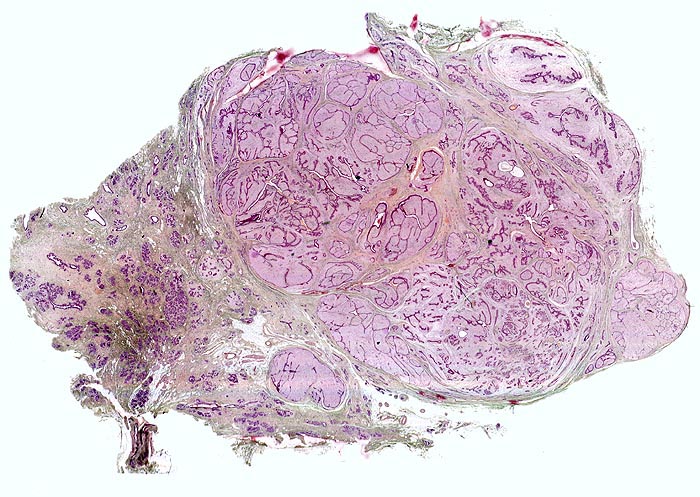

• Zwei scharf begrenzte Tumorknoten.

• Biphasischer organoid aufgebauter Tumor bestehend aus kompaktem zellarmem fibroblastärem Stroma, das in konzentrischen Lamellen um verzweigte, miteinander anastomosierende Drüsenschläuche angeordnet ist.

• Die Drüsenschläuche werden durch das Stroma komprimiert.

• Das Stroma erscheint herdförmig bläulich und aufgelockert durch Muzineinlagerungen.